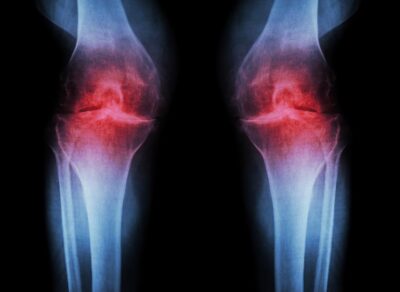

Artrite dolore al ginocchio illustrazione a raggi X

Osteoartrite: lbuprofene e Naprossene antidolorifici possono peggiorare l’infiammazione